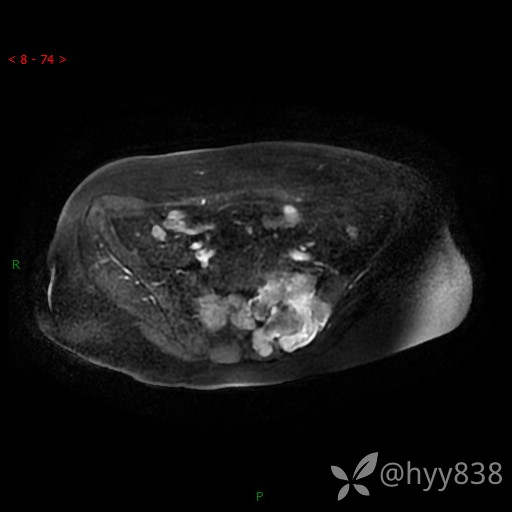

骨盆MRI平扫(T1WI+T2WI+DWI)(外院CT,不能上传)